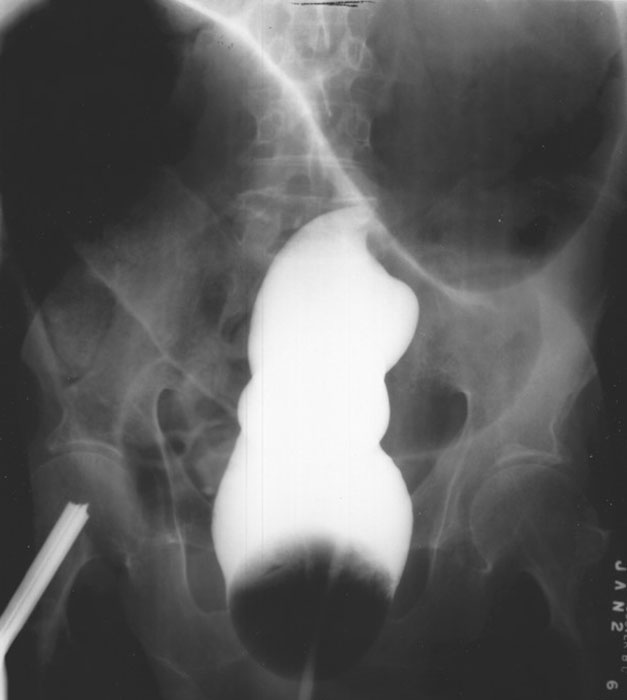

What is volvulus? (twist)

A twisting of a portion of the bowel that may cause obstruction and compromise blood supply.

What are the two major dangers of volvulus?

Bowel obstruction and compromised blood supply.

Obstruction can cause severe distension leading to bowel perforation.

What are common symptoms of volvulus?

Severe abdominal pain, vomiting, and abdominal distension.

How is volvulus treated?

Emergency surgery to untwist the bowel.